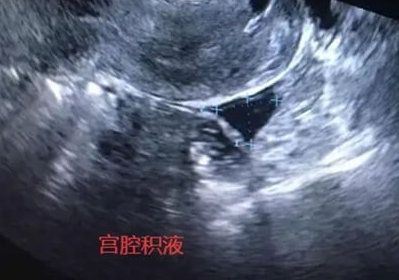

宫腔积液是试管婴儿治疗中常见的并发症之一,指子宫腔内出现异常液体聚集,可能影响胚胎着床,降低成功率。尽管泰国试管婴儿技术成熟,但部分患者仍易出现宫腔积液,这主要与以下因素相关,需结合医疗操作与个体差异综合分析。

输卵管积水:若患者存在输卵管堵塞或积水,试管婴儿治疗中积聚的液体可能逆流至宫腔,形成积液。泰国医院通常会在移植前通过输卵管结扎或切除消除风险,但部分患者因病情复杂或拒绝手术,仍可能残留积液。

积液处理:若发现积液,可通过穿刺抽吸或药物(如抗生素、抗炎药)治疗。